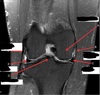

1

Not at all

2

3

4

5

Perfectly